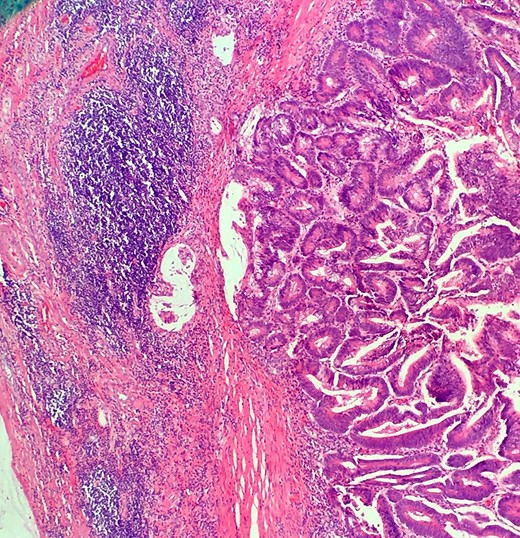

Definitive histological examination showed perforated appendix involved by moderately differentiated mucinous adenocarcinoma (Fig. 5), arising in the background of diffuse tubulovillous adenoma with extensive high-grade dysplasia and showed cellular mucin within the periappendiceal soft tissue (Figs 6 and 7). Proximal cecal mucosal margin and mesenteric margin uninvolved by carcinoma and four periappendicular lymph node was negative for metastatic carcinoma and pathological stage aided for pT4a, pN0. The post-operative course was uneventful. The tumor was staged as T4N0M0 (Modified Astler Coller B3). Patient was referred for oncology and for multidrug adjuvant chemotherapy of 5-fluorouracil, lecovorin and oxalipatin (FOLFOX) was given. Patient was asymptomatic during the 2 weeks, 3 months and 6 months follow up.

This demonstrates mucinous tumor with pushing invasion through the appendiceal wall.

Shows transition of normal cecal mucosa to high-grade tubulovillous adenoma at the appendiceal orifice.